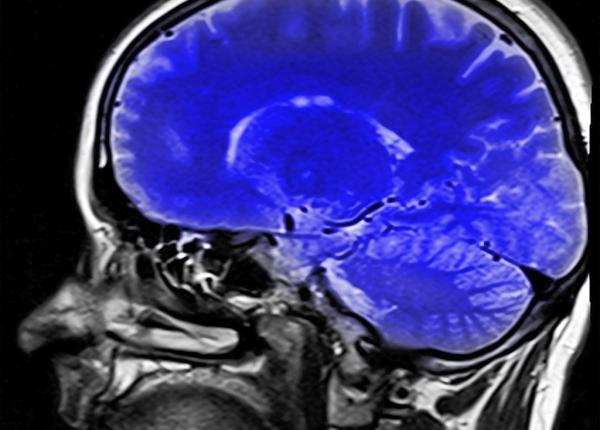

Afecțiuni cerebrale: riscul, măsurat în curând printr-un test de sânge